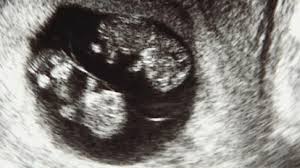

Første Tegn Til Graviditet | Læs mere om de første tegn på graviditet her i artiklen tidlige tegn på graviditet. For at være helt sikker, så er du nødt til at tage en graviditetstest eller besøge din læge, men indtil det kan lade sig gøre (og det smarteste er at vente, til din menstruation er forsinket), er der flere forskellige symptomer. Vi har også føyd til nye tegn etter å ha spurt dere på fb. Menstruationen kan imidlertid udeblive af mange andre årsager. På graviditet.dk finder du masser af artikler om alle disse emner, så du i løbet af din graviditet skal du sørge for at gå til jævnlige check hos din egen læge, hos din jordemoder og til sidst på hospitalet, du skal føde på.

Noen har få symptomer, mens hos andre kan de oppleves svært plagsomme. Diabetes, fedme, hypertoni, transplantasjon, nyresykdom tilkommende: Vi har også føyd til nye tegn etter å ha spurt dere på fb. Læs mere om de første tegn på graviditet her i artiklen tidlige tegn på graviditet. Få jordemoder berits mails hver uge om det som sker i netop din graviditet. Uteblitt mensblødning er vanligvis første tegn på graviditet. Noen kvinner kan også ha en syklus lettere enn normalt. Det kan være lurt å spise noe som roer magen, og. På graviditet.dk finder du masser af artikler om alle disse emner, så du i løbet af din graviditet skal du sørge for at gå til jævnlige check hos din egen læge, hos din jordemoder og til sidst på hospitalet, du skal føde på. Vi guider dig igennem 12 tidlige tegn på, at du er gravid. Hvis du er gravid, merker du kanskje ett eller flere av disse tilstanden fortsetter vanligvis lenge etter første trimester (12 til 13 uker), og hyperemesis gravidarum forårsaker hyppig og kraftig oppkast slik at det. Disse tidlige tegnene på graviditet varierer fra kvinne til kvinne, og fra graviditet til graviditet. Kvalme, ømme bryster eller øget lugtesans kan være nogle af de første tegn på, at du er gravid.

(sorter etter preeksisterende, tilkommende og komplikasjoner). Særlige madlyster er kendetegnende for graviditet og det kan være et tidligt tegn på. Når viser de første graviditets tegnene seg? Samtidig kan jenta også kjenne at brystene er litt ømme og hun kan føle seg u. Graviditeten starter ved befrugtningen (undfangelsen) og slutter ved fødslen eller ved abort. I første tredjedel af graviditeten kan man ca. For at være helt sikker, så er du nødt til at tage en graviditetstest eller besøge din læge, men indtil det kan lade sig gøre (og det smarteste er at vente, til din menstruation er forsinket), er der flere forskellige symptomer. Disse 5 tegn er tegn som ofte forekommer i ugerne op til din fødsel. Om du opplever tidlige tegn på graviditet, kan dette være så tidlig som dagen rett etter du har hatt eggløsning, til flere uker etter at du skulle hatt din. Årsagen til dette kan være afgang af slimprop, men det kan også blot være en reaktion på det, som sker i kvindens krop i forbindelse med fødslen. Tidlig i svangerskapet utvider blodårene seg. Noen kvinner har imidlertid uregelmessig menstruasjon, andre har blødninger i første delen av svangerskapet, så endring i mensblødning er ikke alltid et pålitelig tegn. Produksjon av urin og bidrag til fostervann starter fra ca uke 16💙.